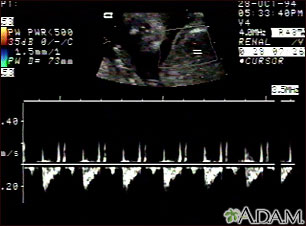

Este es un ultrasonido fetal normal que muestra un patrón de los latidos cardíacos del feto. Algunos equipos de ultrasonido tienen la capacidad de enfocar áreas diferentes del corazón y evaluar los latidos del mismo, lo cual es útil para el diagnóstico temprano de las anomalías cardíacas congénitas.